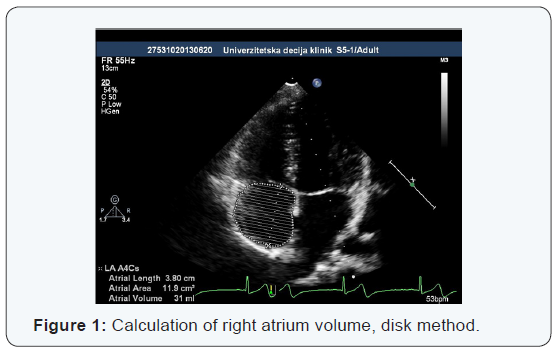

The volume of the right atrium

The best indicator of morphological changes in the right atrium in a variety of hemodynamic disorders is its volume, that is, volume value indexed in relation to the surface of the body - RAVI (Right Atrial Volume Index). In the states of hypovolemia or volume overload as is the case in the presence of an atrial septal defect, there are significant changes in the dimensions of the right atrium and ventricle. However, studies have shown a very rapid and significant reversibility of these changes after transcatheter closure of ASD. In our study in healthy children, we found the average value of RAVI from 23.06 ± 6.2 ml / m2, which is not significantly different from the reference values obtained in the other studies.

In the study Kucinska [7], the changes in children with ASD after transcatheter closure of defect Amplatzer septal occluder, were examined. Within 24 hours after the closure, there was a significant normalization of dimension DA and DV, while in the next three months, most of the dimensions of the right cardiac cavities, returned to normal values. A period a bit over two years, after the removal of the volume load, was needed to normalize the transverse diameter of the right atrium and the diameter of the right ventricular outflow tract. Nevertheless, it has been found that in children with transcatheter closed ASD, significantly faster hemodynamic recovery occurs, in relation to children in whom ASD was closed surgically. In new echocardiography recommendations in the assessment of morphological characteristics of the right atrium, RAVI of normal value of 21ml / m2 is increasingly stated as a good indicator.